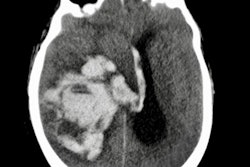

Less-intrusive alternatives to autopsy, such as CT angiography, have demonstrated potential in ascertaining the cause of death of patients. With this in mind, the group set out to determine the extent to which postmortem CT could facilitate or replace autopsy.

The researchers performed whole-body postmortem CT scans on 86 cadavers before autopsy. Postmortem CT helped the radiologists significantly improve clinical diagnosis as to the cause of death, type of pathology, and anatomic region involved.